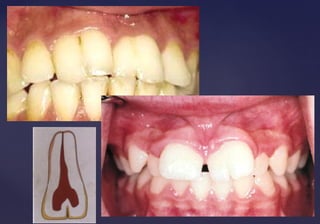

TetraciclinasTetraciclinas

Son antibióticos que comenzaron a ser

desarrollados en 1948, su ingesta por parte de

mujeres embarazadas o niños a corta edad

produce alteraciones dentarias.

 Los cambios de color son

provocados por el efecto

secundario de las tetraciclinas,

forman bandas de pigmento

fluorescente en el interior de

las piezas dentarias y también

inhiben la calcificación.

 El diente se torna amarillo o

marrón grisaceo.

 Tinción por tetraciclina moderadaTinción por tetraciclina moderada  Tinción por tetraciclina leveTinción por tetraciclina leve

Tinción por

tetraciclina severa

DENS IN DENTEDENS IN DENTE::

 Invaginación de las células delInvaginación de las células del

epitelio interno del órgano delepitelio interno del órgano del

esmalte, por enclavamientoesmalte, por enclavamiento

del ectodermo hacia la papiladel ectodermo hacia la papila

dentaldental

 El esmalte que cubre la superficieEl esmalte que cubre la superficie

de la cavidad da la apariencia dede la cavidad da la apariencia de

un diente que contiene otroun diente que contiene otro

pequeño en su interior.pequeño en su interior.